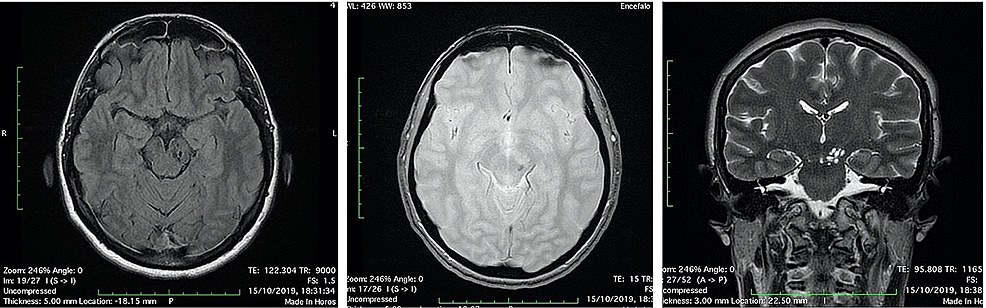

The patient was discharged and she continued the treatment for the scalp lesion and gradually recovered from vertigo. She repeated CT and MRI exams to follow the midbrain lesion up: a CT scan after one month (Figure 5) and a MRI scan after four months (Figure 6). A significant volume reduction of the midbrain lesion was observed.